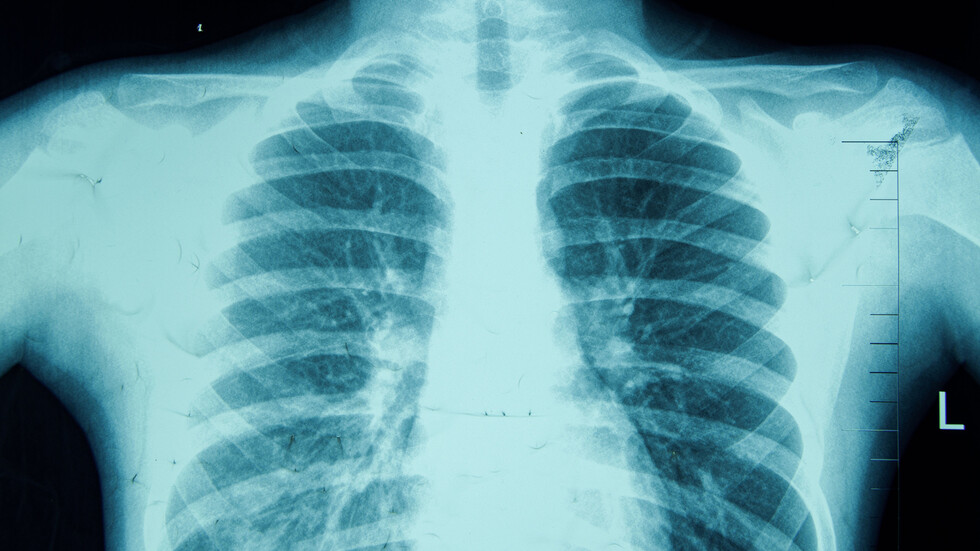

130 години от откриването на рентгеновите лъчи

Той подчерта, че най-честата рентгенография си остава тази на гръдния кош, а при съмнение за онкологично заболяване се прави компютърна томография. ЯМР се прави за всички системи, но най-често е за изобразяване на централна и периферна нервна система.